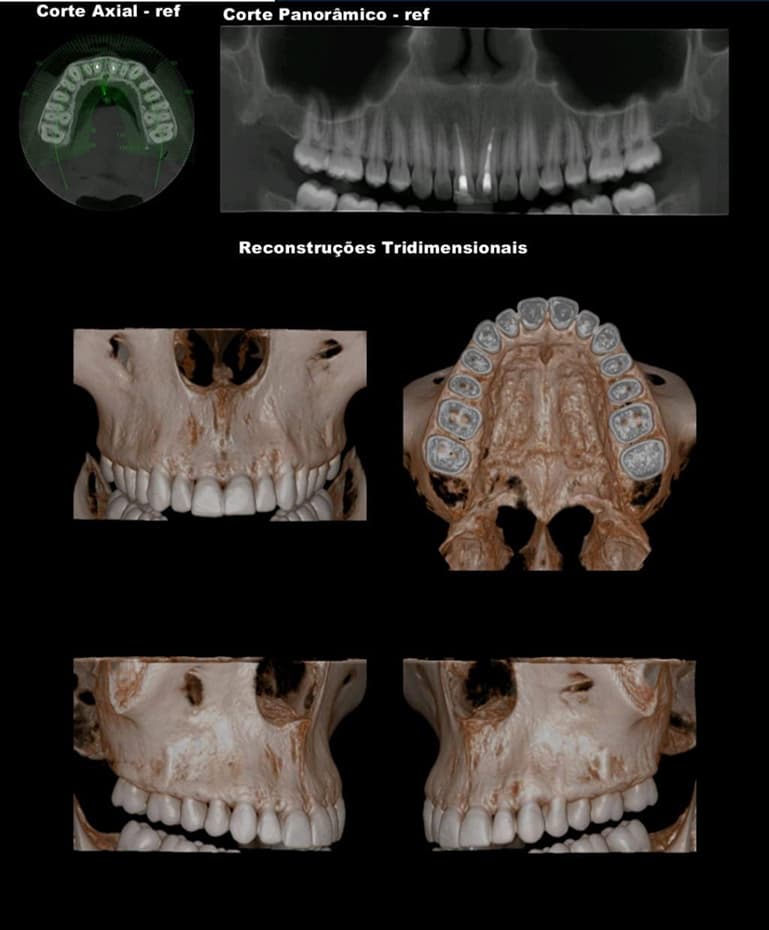

TOMOGRAFIA COMPUTADORIZADA DE ALTA RESOLUÇÃO por feixe Cone Bean - MORITA X800

- MAXILA TOTAL

- MANDÍBULA TOTAL

- FACE - SEIOS DA FACE